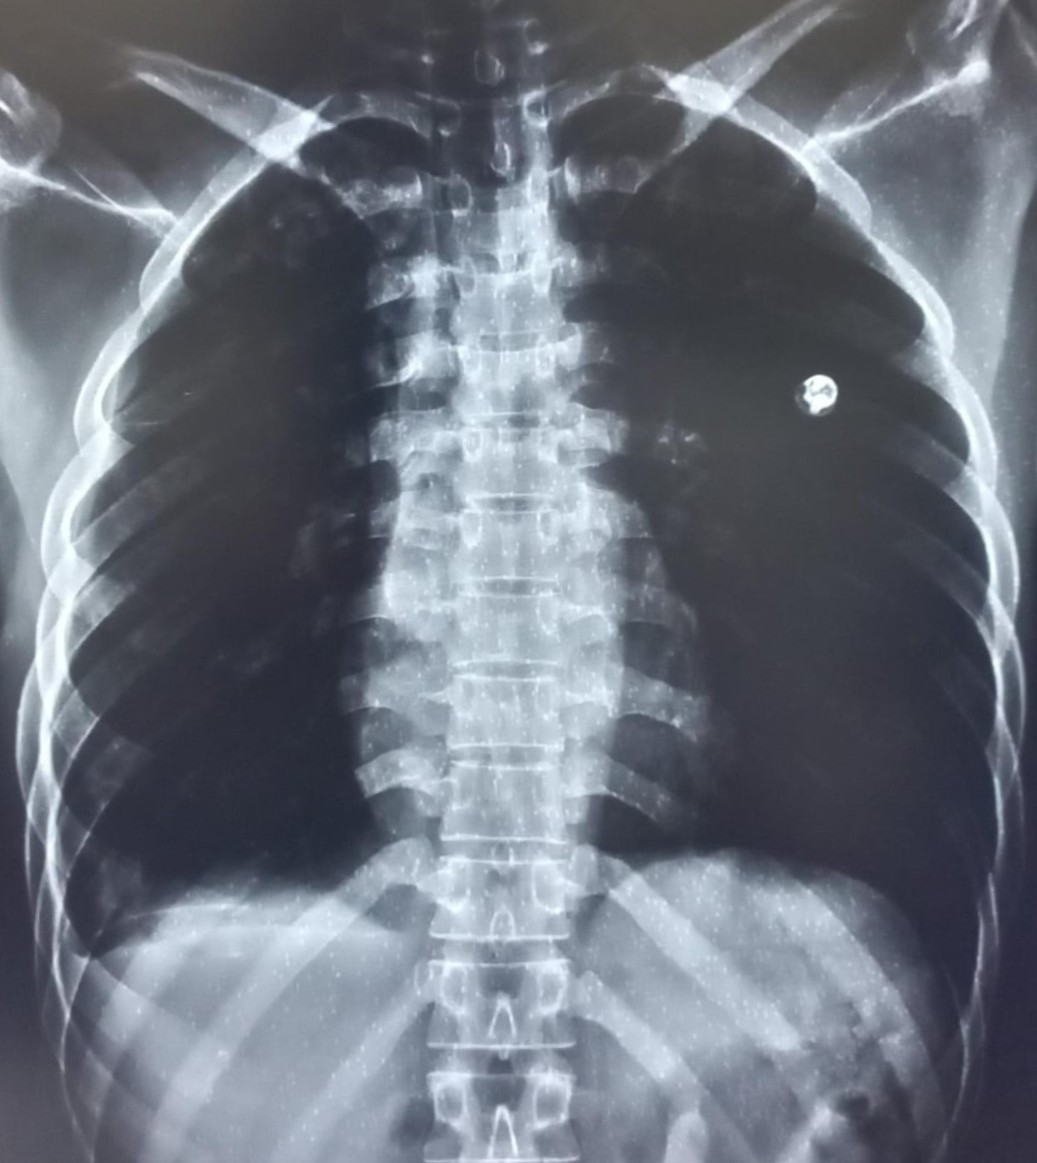

| 4404 | IGGMC, Nagpur, Nagpur | P2 | 29-68 | Gauri Rathod | Consent taken on Paper | 12 Yrs. |

Provisional Diag : Lower Respiratory Tract Infection

Final Diag : LEFT LOWER ZONE INFILTRATIONS |

Non-TB Case (Confirmed) | Left Mid Zone Radiopacity/ clothing Artifact | Abnormality visible on x-ray |